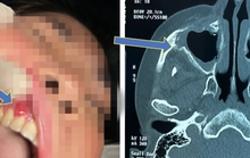

Kết luận nguyên nhân gây bệnh hoại tử xương hàm mặt sau mắc Covid-19

Tình trạng hoại tử xương hàm mặt trên bệnh nhân sau mắc Covid-19 được Hội đồng chuyên môn đánh giá là một bệnh lý ít gặp nhưng không phải là một bệnh lạ.